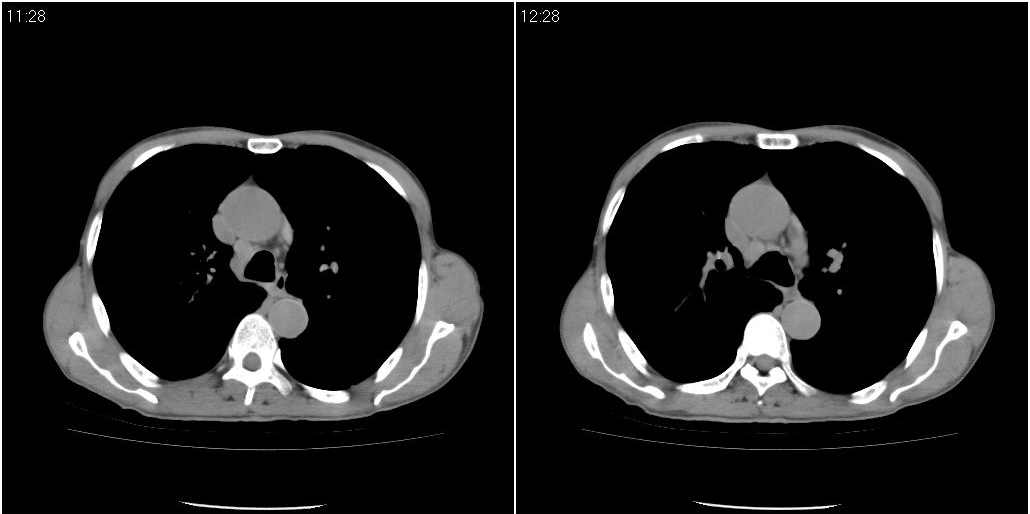

标题: ct增强:

[本贴已被 fanshl 于 2010-3-30 7:14:31 修改过]

右肺中叶阻塞性不张及肺炎,高度怀疑支气管占位,建议纤支镜检查!

考虑右肺中叶感染。左肺下叶支扩。

右中肺阻塞性炎症,建议纤支镜!双下支扩感染。

1)右肺中叶慢性炎症并支气管扩张,节段性肺不张。2)两肺下叶支气管扩张。